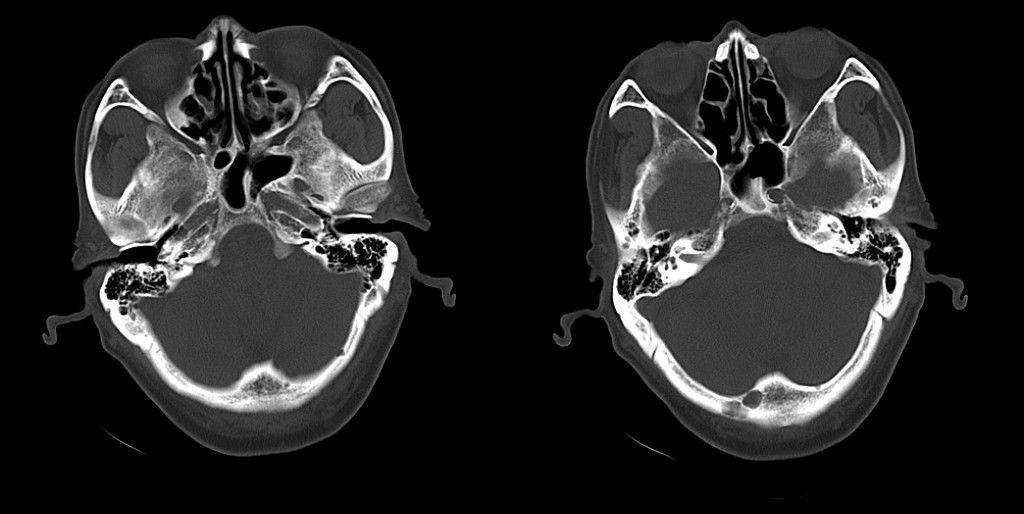

标题: CT25311:箭头所指是问题么?

该患者因头疼来诊,发现枕骨不规则缺损。

不除外转移

蛛网膜颗粒压迹,讨论过很多了,年龄大了不考虑lch;脑白质疏松。